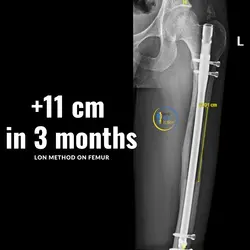

With the combined method (Lon method), an internal nail and an external fixation are attached which allow the bone to be extended from the outside.